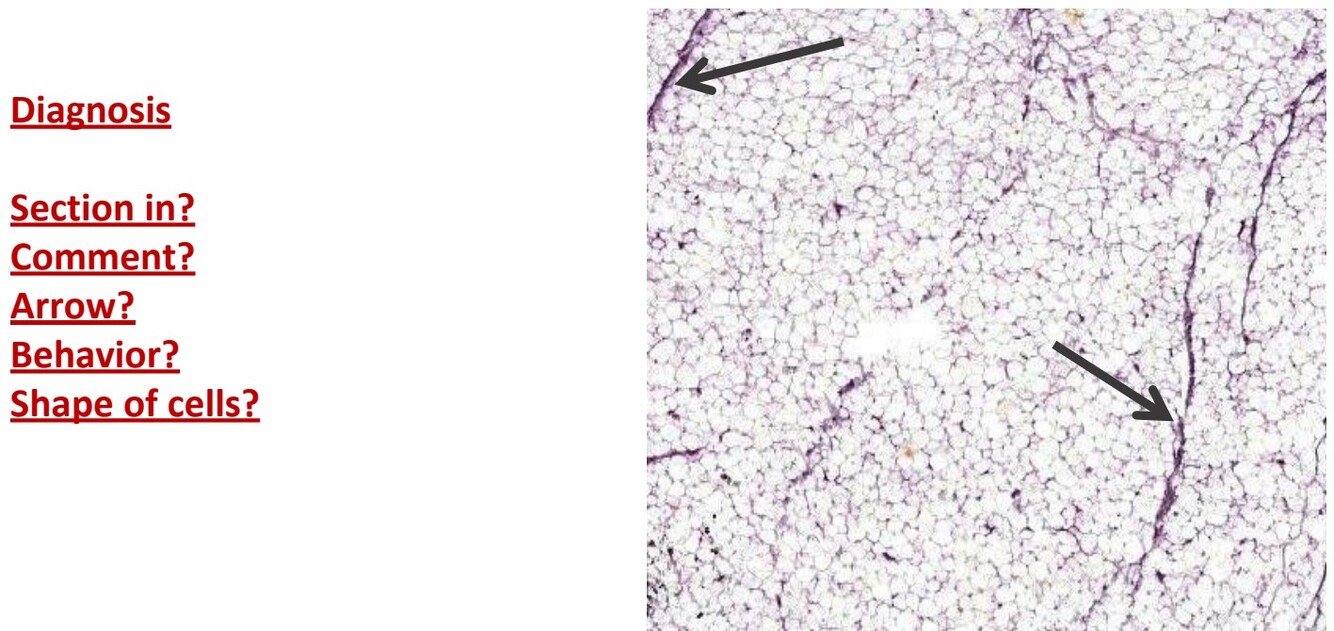

Lipoma

Section from Benign tumor

Fibrous capsule surrounds tumor creating fibrovascular septa

Lobules are formed of mature fat which are polygonal

arrow points to septa